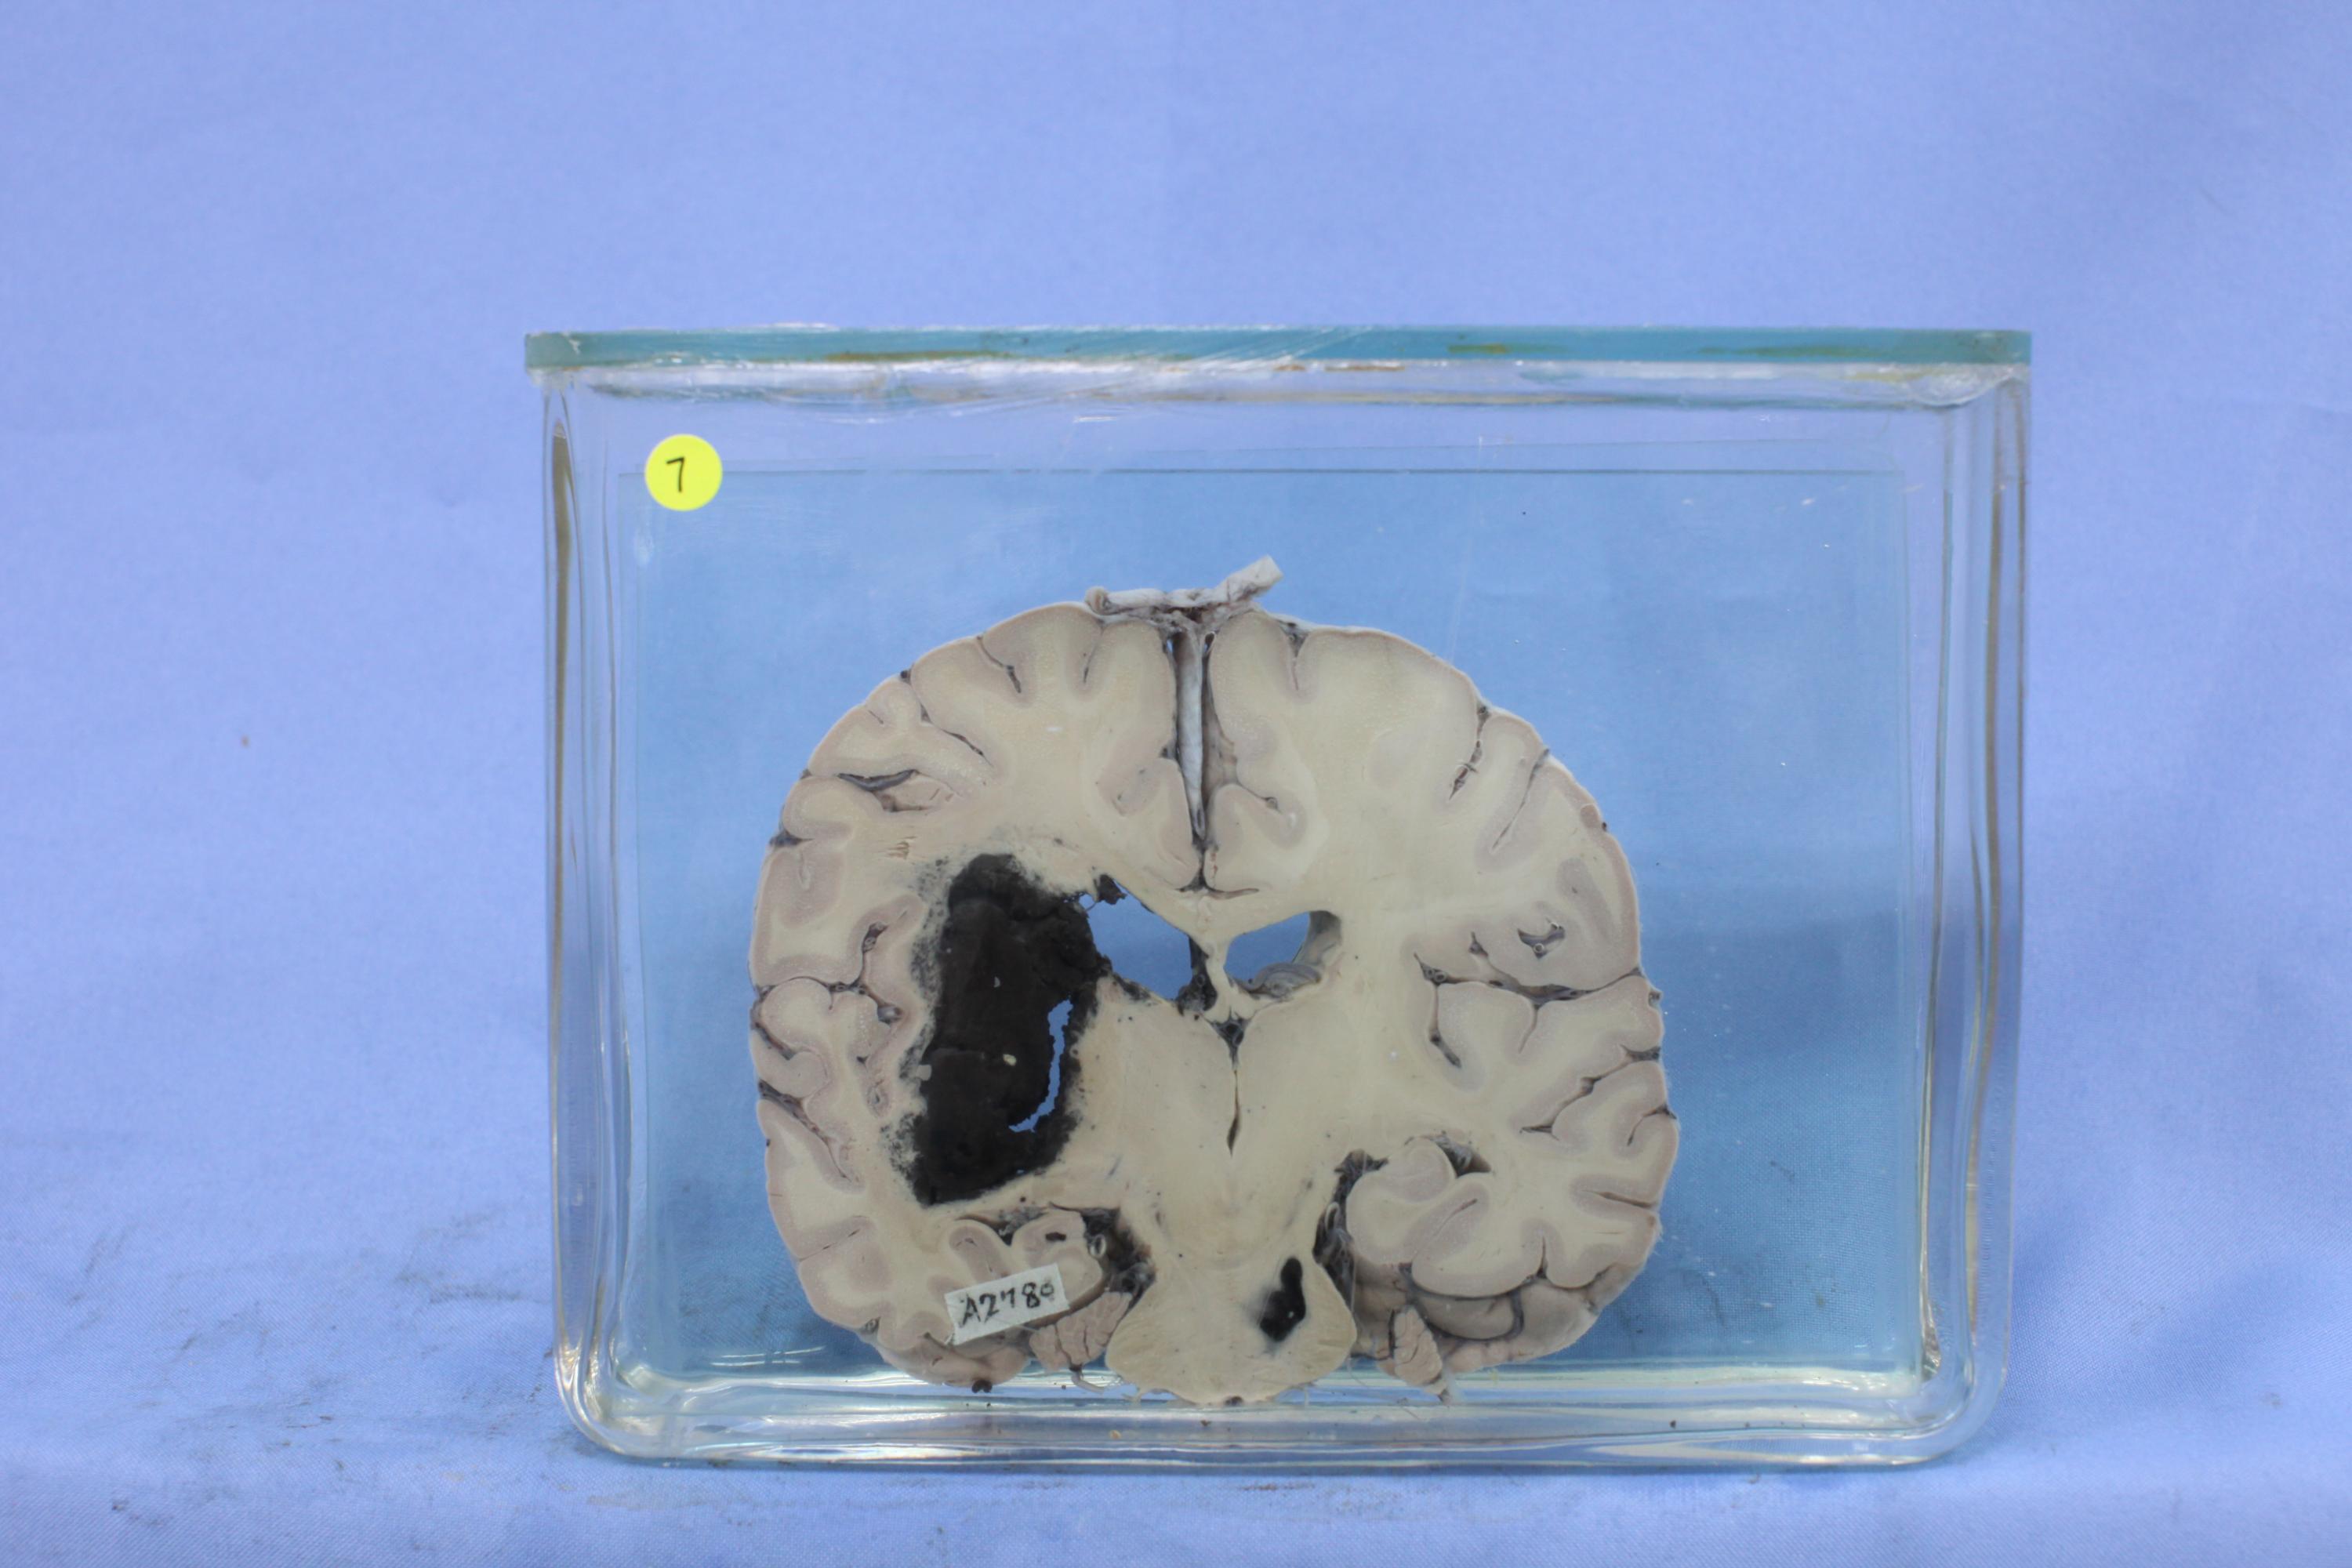

神经疾病-58-7. 左侧丘脑外侧白质、对侧中脑小灶性出血

左侧丘脑外白质见5×10cm黑色凝血块,局部组织破坏,右侧桥脑见1.51×1cm黑色凝血块伴组织破坏。